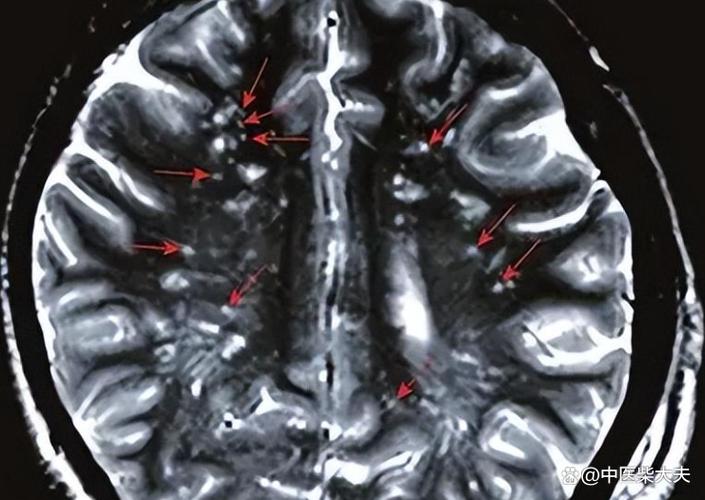

“缺血灶”和“脑腔梗”都是脑组织曾经缺血坏死的“遗迹”或“疤痕”,它们在核磁共振(MRI)上表现为信号异常的区域,是医生判断脑血管健康状况的重要依据。

缺血灶是一个比较宽泛的术语,可以把它理解为大脑某个区域曾经发生过缺血事件,并留下了一个“印记”,这个印记在影像学上表现为一个边界不清、形态不规则的异常信号区。

- 形态:通常形态不规则,与受累血管的供血区不完全吻合。

腔隙性脑梗塞是缺血灶中一个特定类型,有非常明确的定义和特征。

- 位置:发生在大脑半球深部、脑干等部位,这些区域的血管比较细长,被称为“穿通动脉”或“终末动脉”。

- 大小:病灶非常小,直径通常在 5毫米到20毫米 之间。

- 形态:病灶形态相对规则,呈圆形或卵圆形,像个小“豆子”或“小坑”。